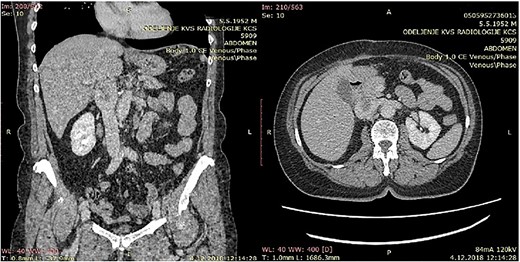

CT of the abdomen that shows a retroperitoneal tumor mass that involves IVC above the renal and under the liver veins.

All five patients underwent surgical resection of primary LMS. A majority of patients had involvement of only their suprarenal IVC (three patients; 60%). Two patients (40%) had tumor involving infrarenal segment IVC (I segment). IVC was reconstructed using Dacron grafts in all patients (five patients; 100%). A bypass was done on the left hepatic vein of one patient, while the other two patients required reimplantation of the renal veins directly into the graft (while one of them, the other to the left of the RV). Additional organ resection was required in one patient (20%): in whom cholecystectomy was performed and partial liver resection due to metastasis in the left lobe of the liver. The mean total duration of surgery was 212 minutes, and the average estimated blood loss was 1126 ml.